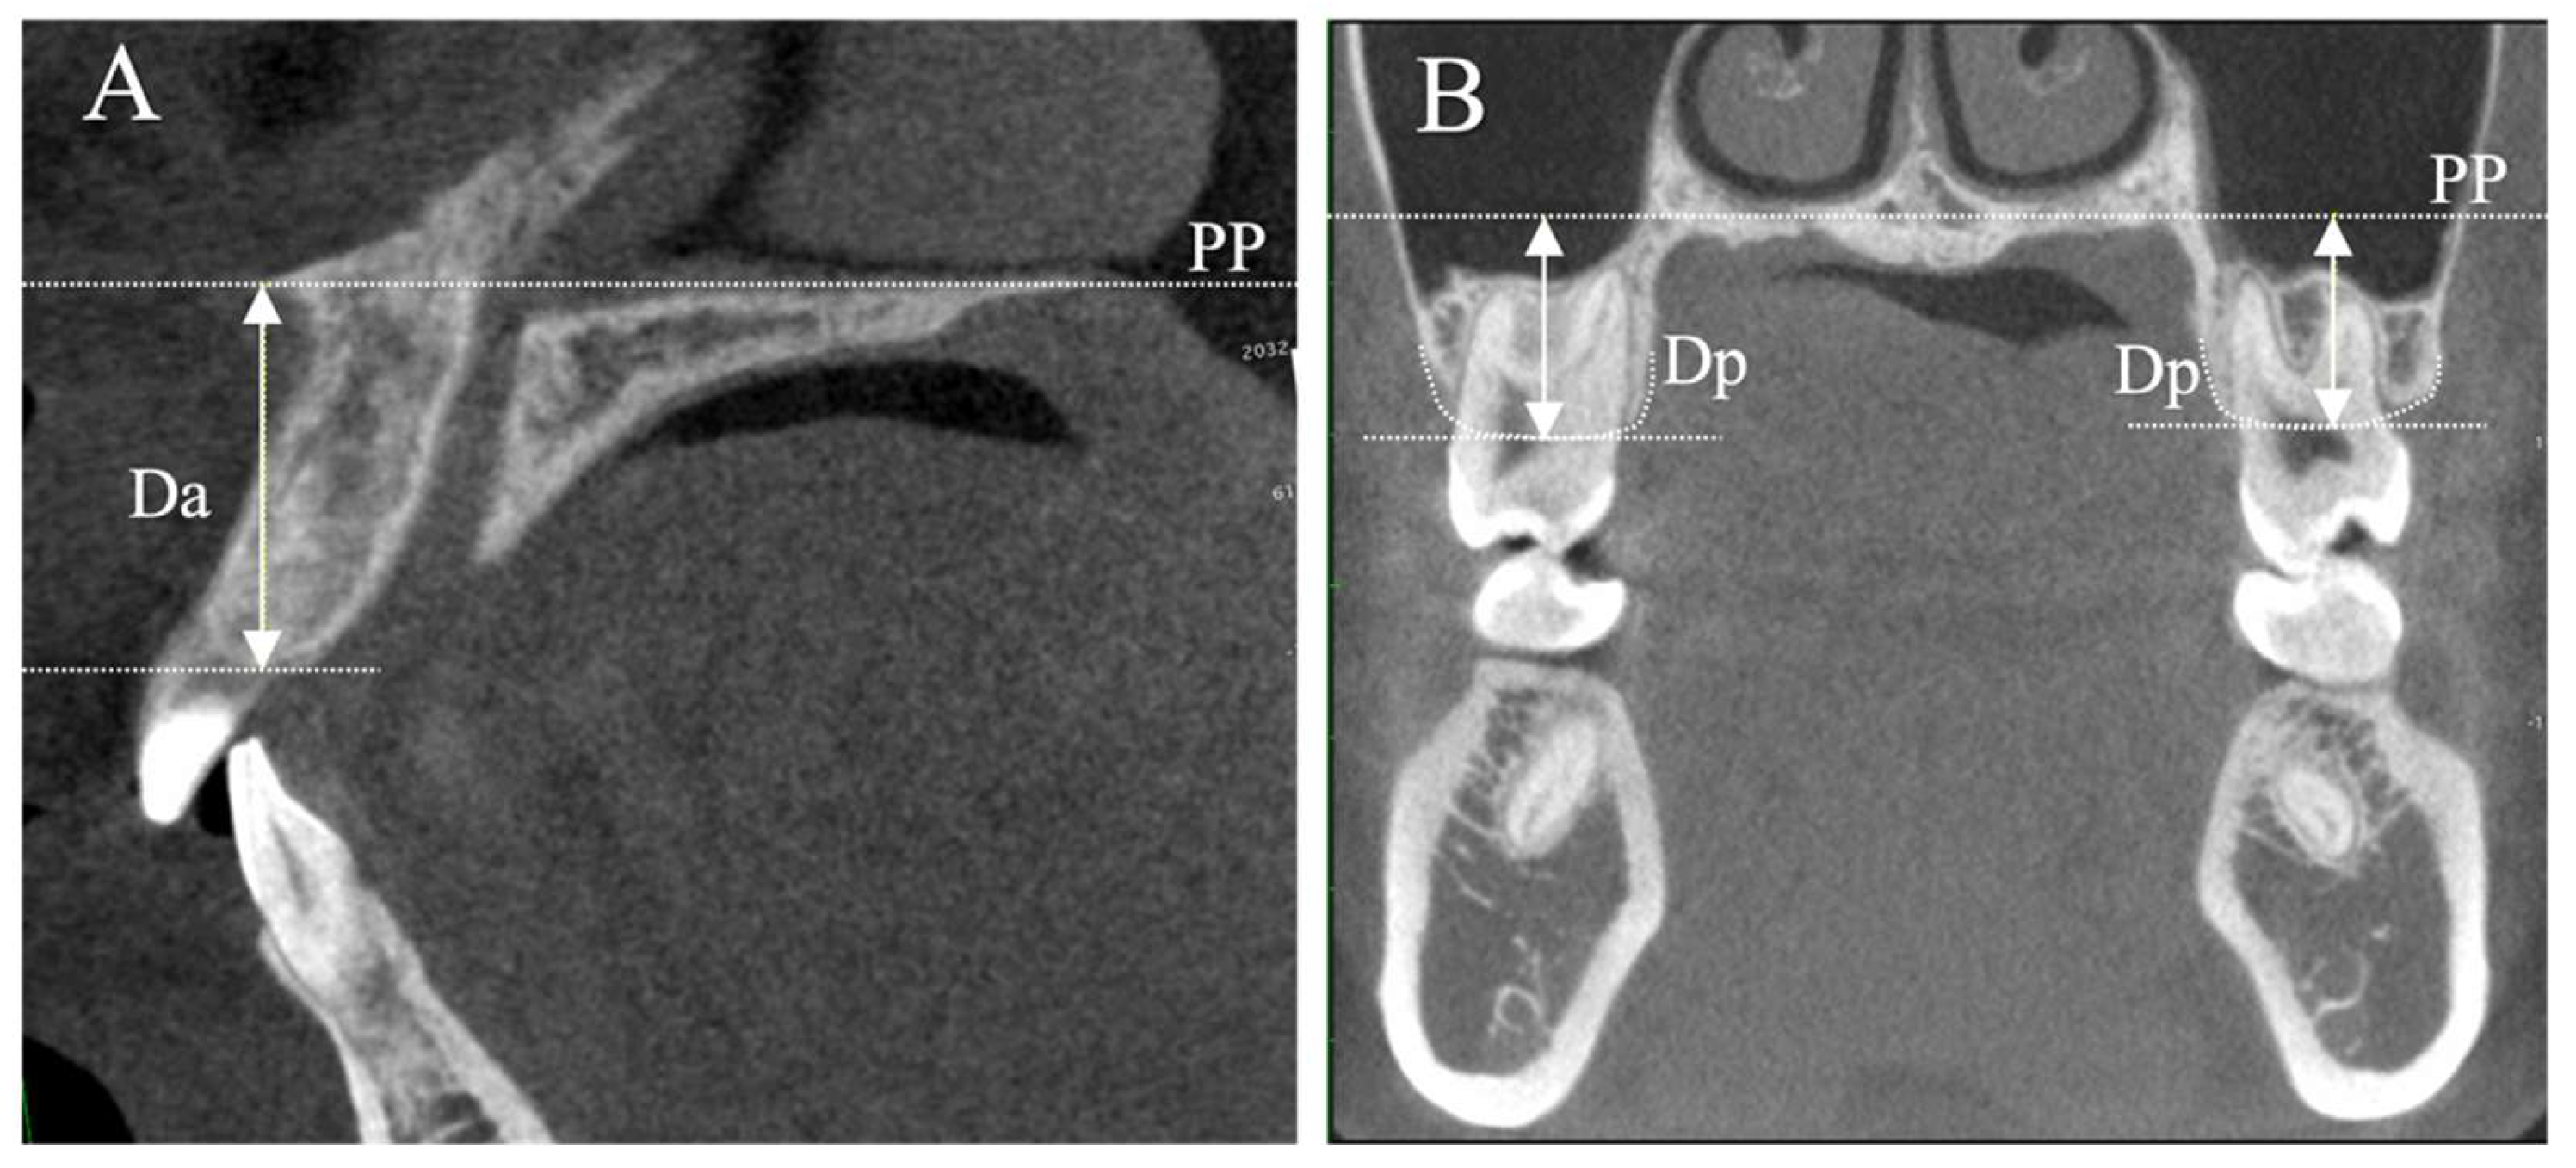

2.2. Measurements

| Da (mm) | 18.67 ± 2.21 | 19.76 ± 2.66 | 0.130 |

| Dp (mm) | 14.12 ± 1.35 | 15.09 ± 1.38 | 0.016 * |